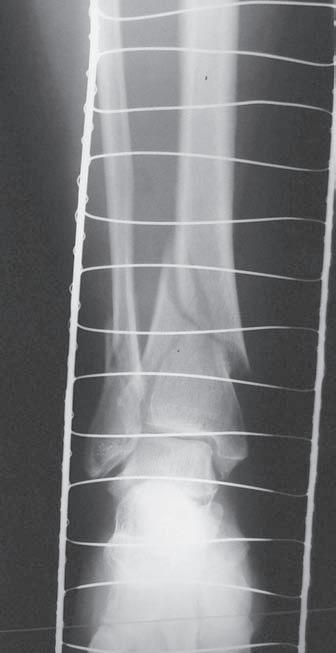

O br. 1. 2 S k iagram hl ezna v pře d oza d ní proje k ci (a) – d is k rétní z d vojení k ontury mediálního kotníku (viz šipka), jinak zdánlivě normální nález; skiagram hlezna v boční projekci (b) – fraktura zadní hrany tibie a zadní části vnitřního kotníku, subluxační postavení v talokrurálním kloubu (viz šipka) ab

Obr. 2.1 Jednoduchá příčná zlomenina tibie, typ A podle AO klasifikace. Současně je přítomná nedislokovaná nitrokloubní zlomenina proximální části

Obr. 2.2 Spirální zlomenina distální části tibie a šikmá zlomenina zevního kotníku. Typ A podle AO klasifikace